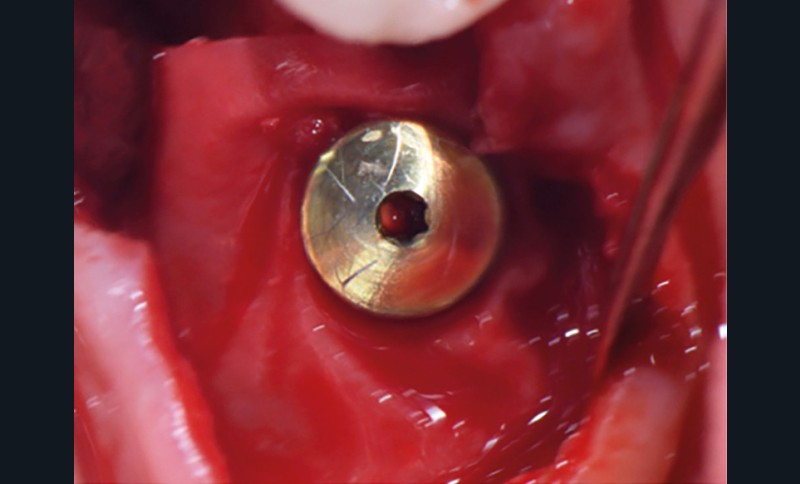

- Péri-implantite sur l’implant 47, diagnostiquée en août 2022

- Implant posé en 2017

- Nobel Replace Select RP (4,1 x 10 mm)

La couronne a été déposée et une vis de couverture mise en place. La patiente a reçu un nettoyage supra-gingival général avec une attention particulière pour l’implant 47, et une irrigation locale avec du gel de chlorhexidine et du peroxyde d’hydrogène pour réduire l’inflammation des tissus. De l’amoxicilline (3 x 500 mg) a été prescrite, à commencer la veille de l’intervention chirurgicale.